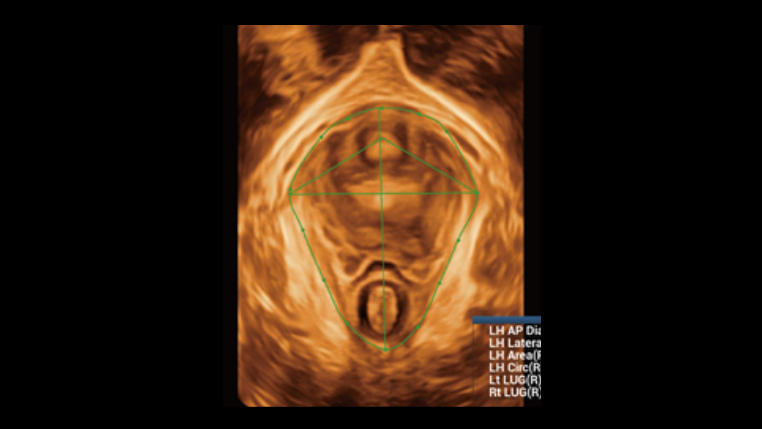

Smart FLC automatically detects the number of follicles and calculates each volume from a 3D ovarian volume image, assuring accurate assessment of follicles, essential for IVF exams.